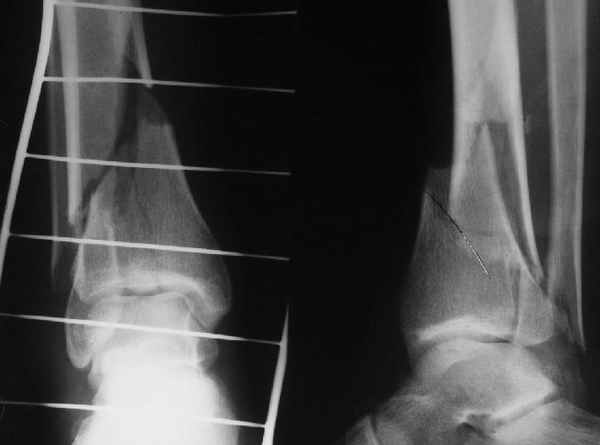

Еще, кстати, о фиксации лодыжки, если уж непременно хочется ее отдельно стабилизировать - при таком характере перелома замечательно должен сработать предложенный проф. Лазаревым с соратниками способ фиксации напряженной V-образной спицей. Опять же, открытая репозиция не нужна, мы делаем непрямую репозицию именно аппаратом. В приложении пример, там перелом малоберцовой куда менее поперечный, чем в данном случае, но все равно получилось закрыто без пластинки.

A propos fibular fixation if one is eager to stabilize it separately. In the fracture pattern a way of closed fixation by V-shaped stressed wire (advanced by colleagues from Moscow, prof. Lazarev A.F. et al.) must be excellent. We use indirect closed reduction by the external fixator. Example attached, that fibular fracture is even more suitable for plating but the wire did the job.